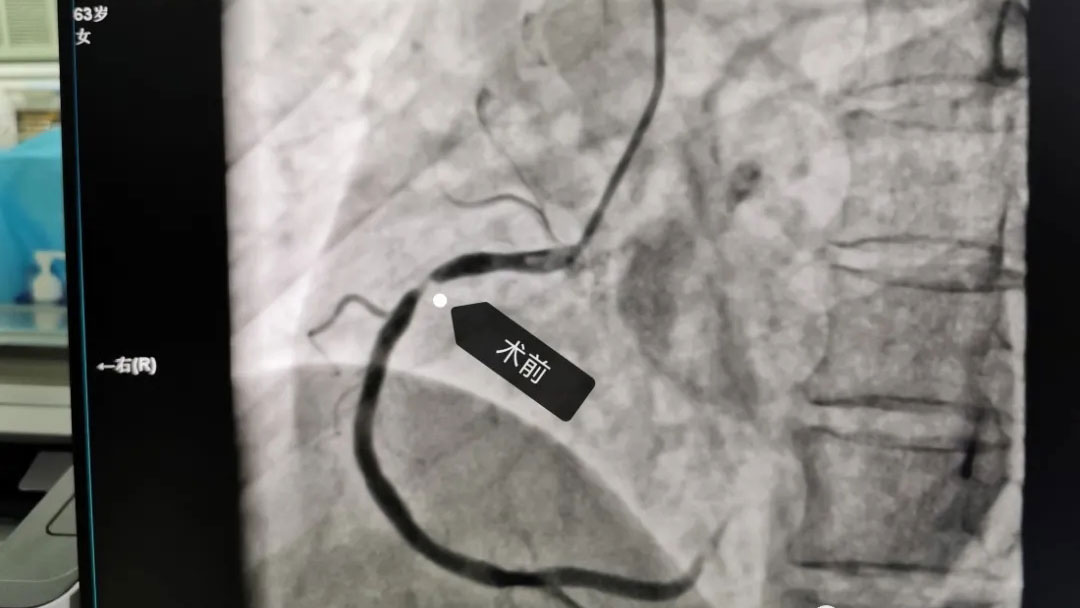

此次赠送锦旗的周某,为本周冠状动脉造影术后的患者,深深感受到术前术中术后带来的快捷和方便,7月14日,周某携其家属为感谢武汉亚心总医院王琛主任及来凤县中心医院心内科团队,专程送来了一面锦旗,以示感谢。

据了解,来凤县中心医院常规开展冠状动脉造影及冠脉支架植入术以来,极大提高了冠心病的诊疗水平,而且还常规开展远桡动脉穿刺,大大改善近端桡动脉穿刺带来的“肿、胀、痛”等术后不适。取得了良好的诊断和治疗效果,赢得了广大病患者的赞誉。